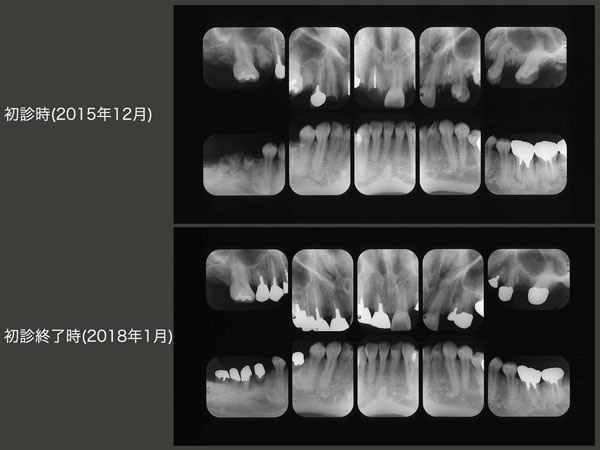

初診時および初診終了時のデンタルX線写真の比較.単純に抜歯してインプラントあるいは義歯を装着するより,「もったいない」精神にのっとり天然歯をできるだけ保存して,もう一度利用する治療のほうが好ましいと考えている.